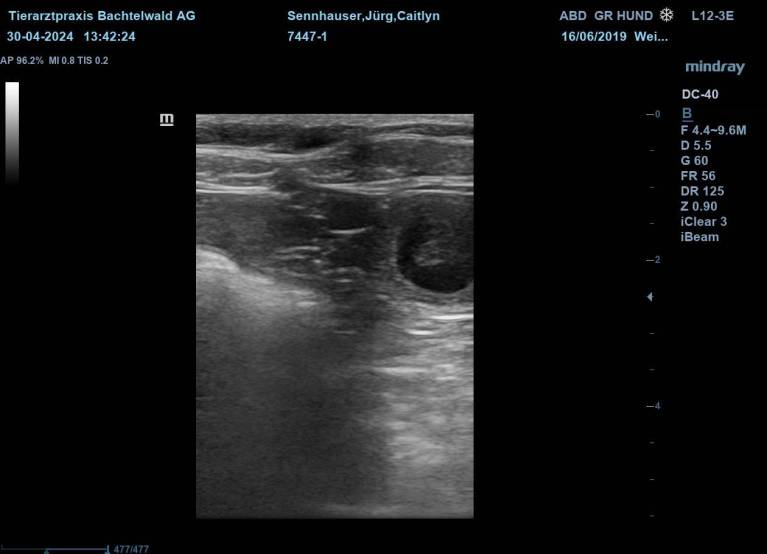

Caitlyn wurde Anfang April mit dem Xanadu "Zane" verpaart.

Nun heisst es "gespannt warten" bis wir in 3 Wochen den Ultraschall machen werden.